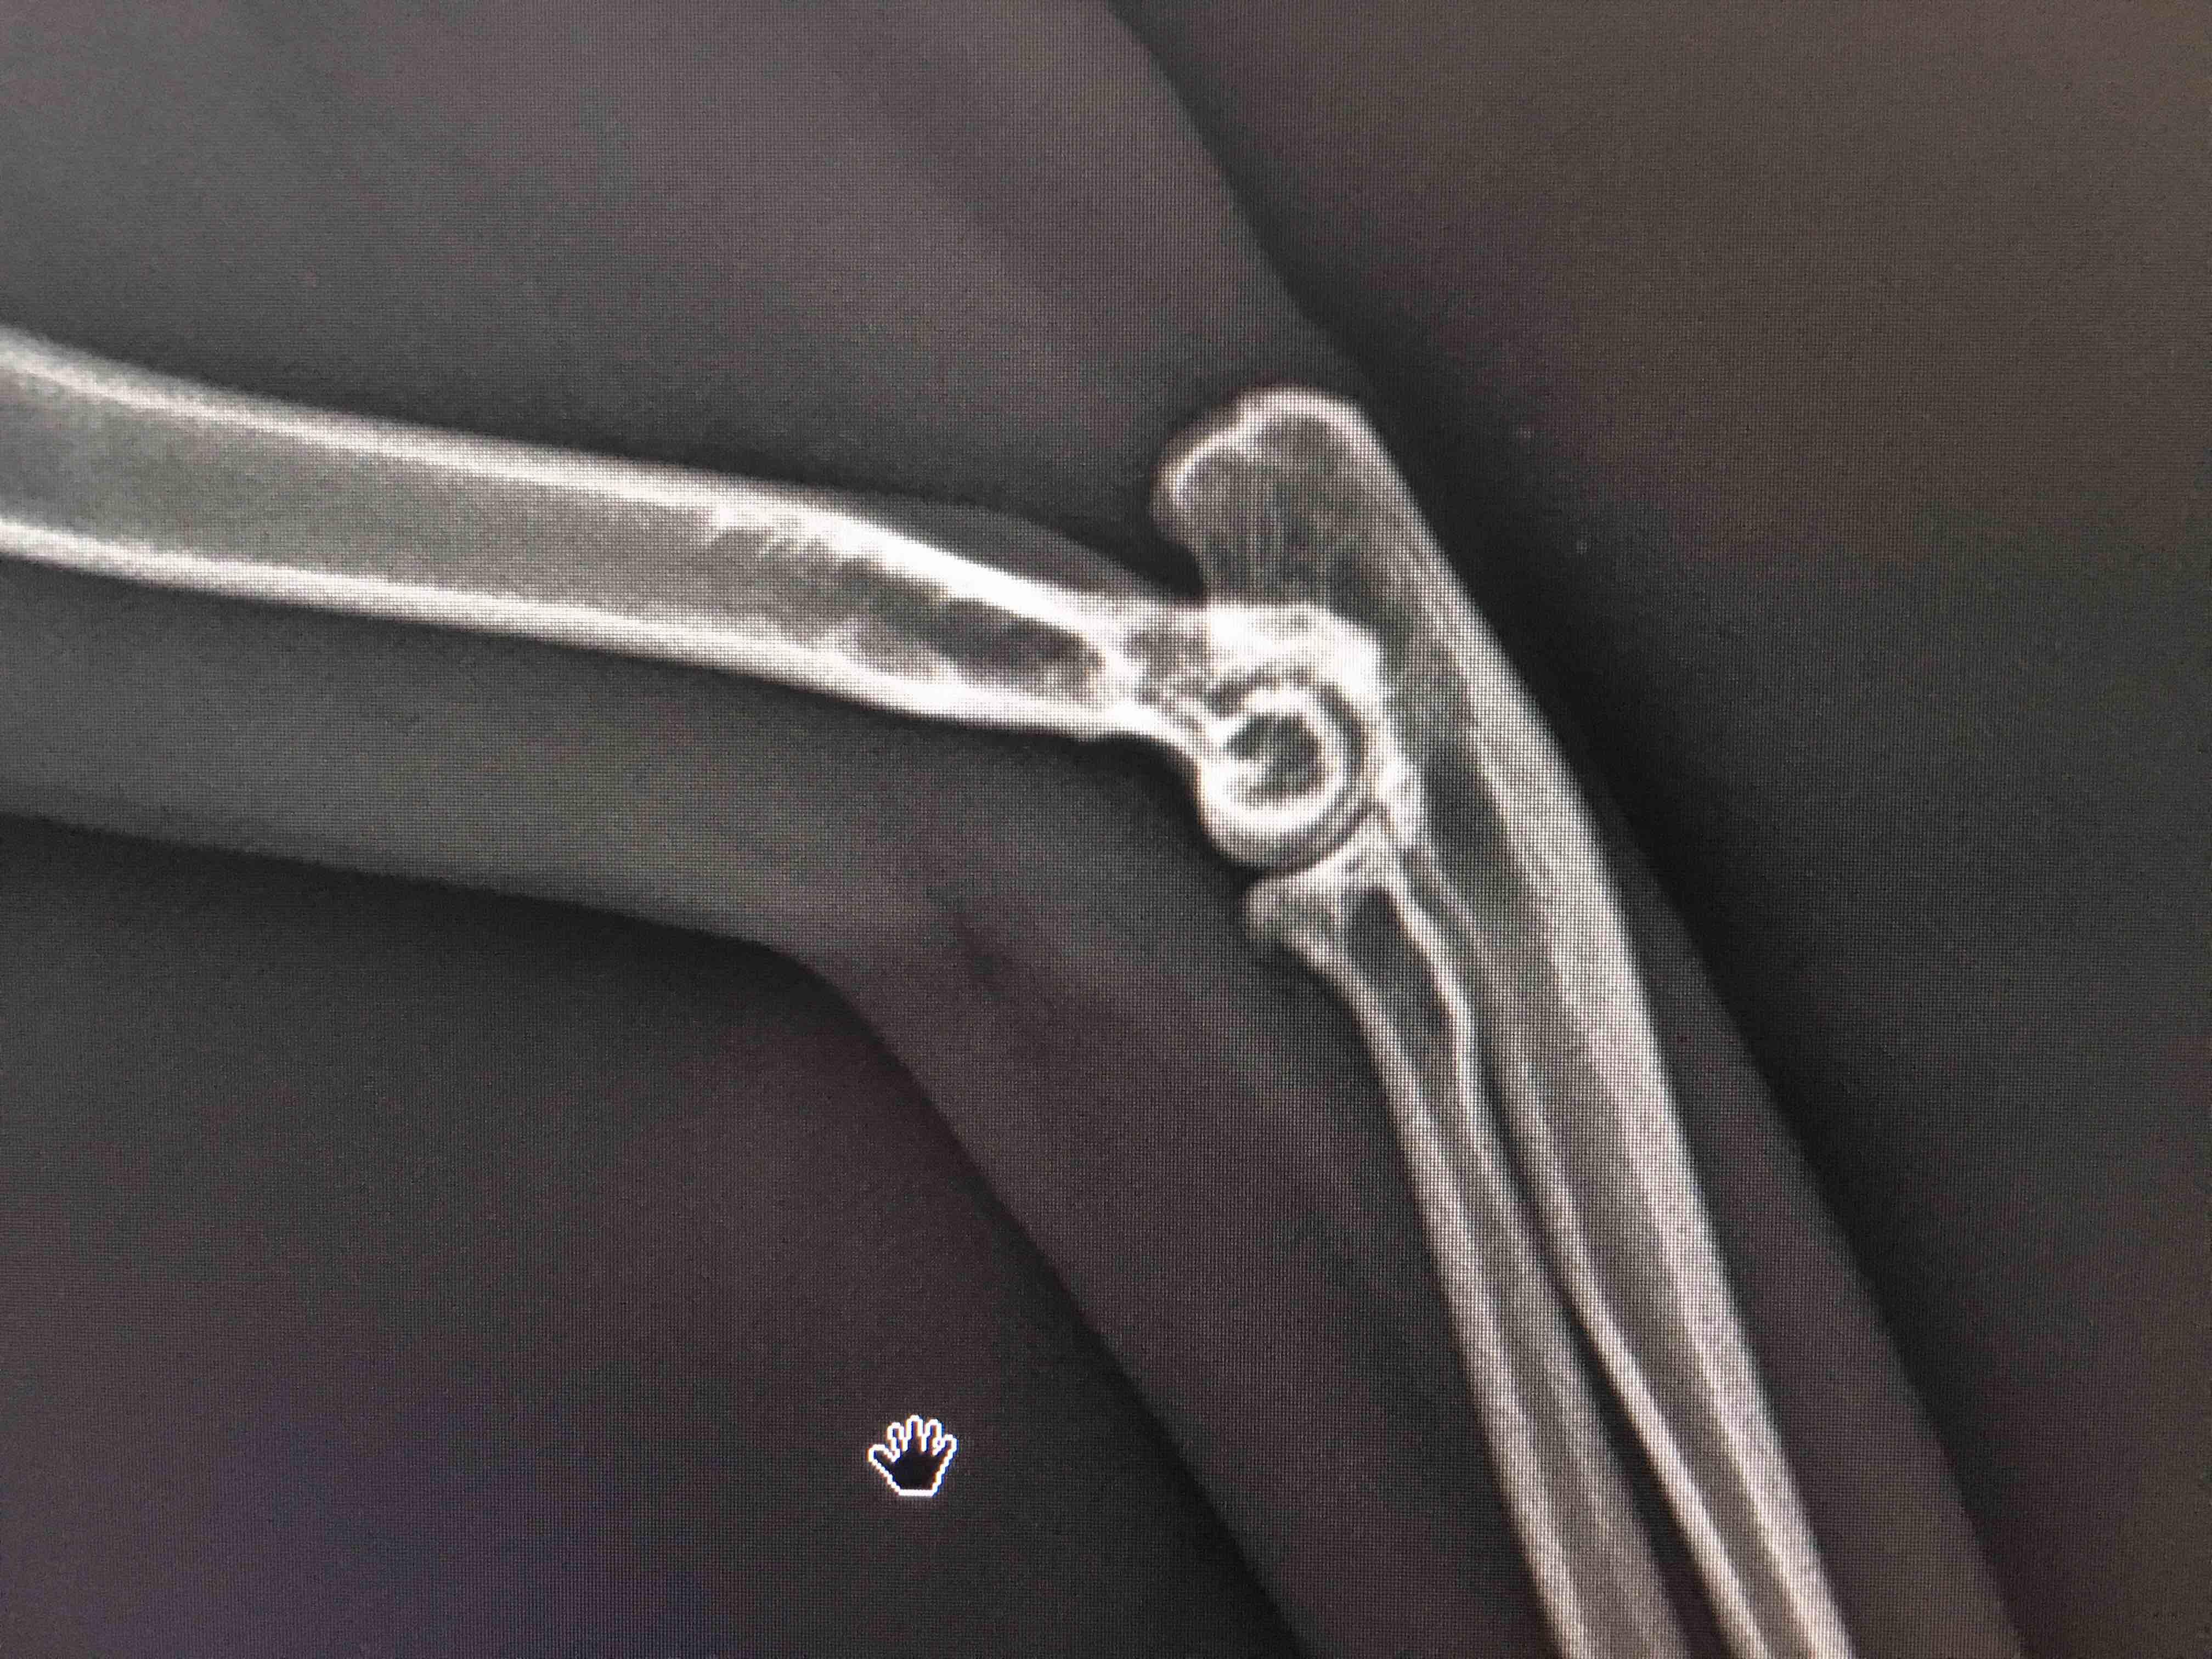

My 3 years old female Scottishfold(heterozygous) cat can’t step on her right paw after she wake up but after 20-30 seconds she can step on her paw.She is in this condition for 1 months.She can run,jump(not too high it’s about 70-80cm) and play like normal cat but she prefer not to bend her right paw.But she can bend it if she want.But she prefer left paw.So I went to vet. for x-ray.He said degeneration has started and it’s because of OCD.What can I give her to slowdown degeneration process?